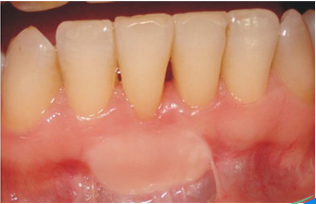

Tedavi Sonucunda Ne Elde Edilir?

Tedavi sonrasında dişler temiz, dişeti açık pembe renkli, sert kıvamlı ve kanamasızdır. Eğer hastalığa bağlı çok ileri kemik yıkımı oluşmuş ise operasyon sonrasında dişlerin boyları uzayabilir. Ancak dişleri destekleyen dokular sağlıklıdır. Bugün elimizdeki teknik imkanlar periodontal problemlerin hemen hepsini çözebilecek düzeydedir. Ancak diş çevresinde kalan kemik miktarı tedavi edilemeyecek seviyede ise, diş çekimi de tedavi planına dahil edilir.